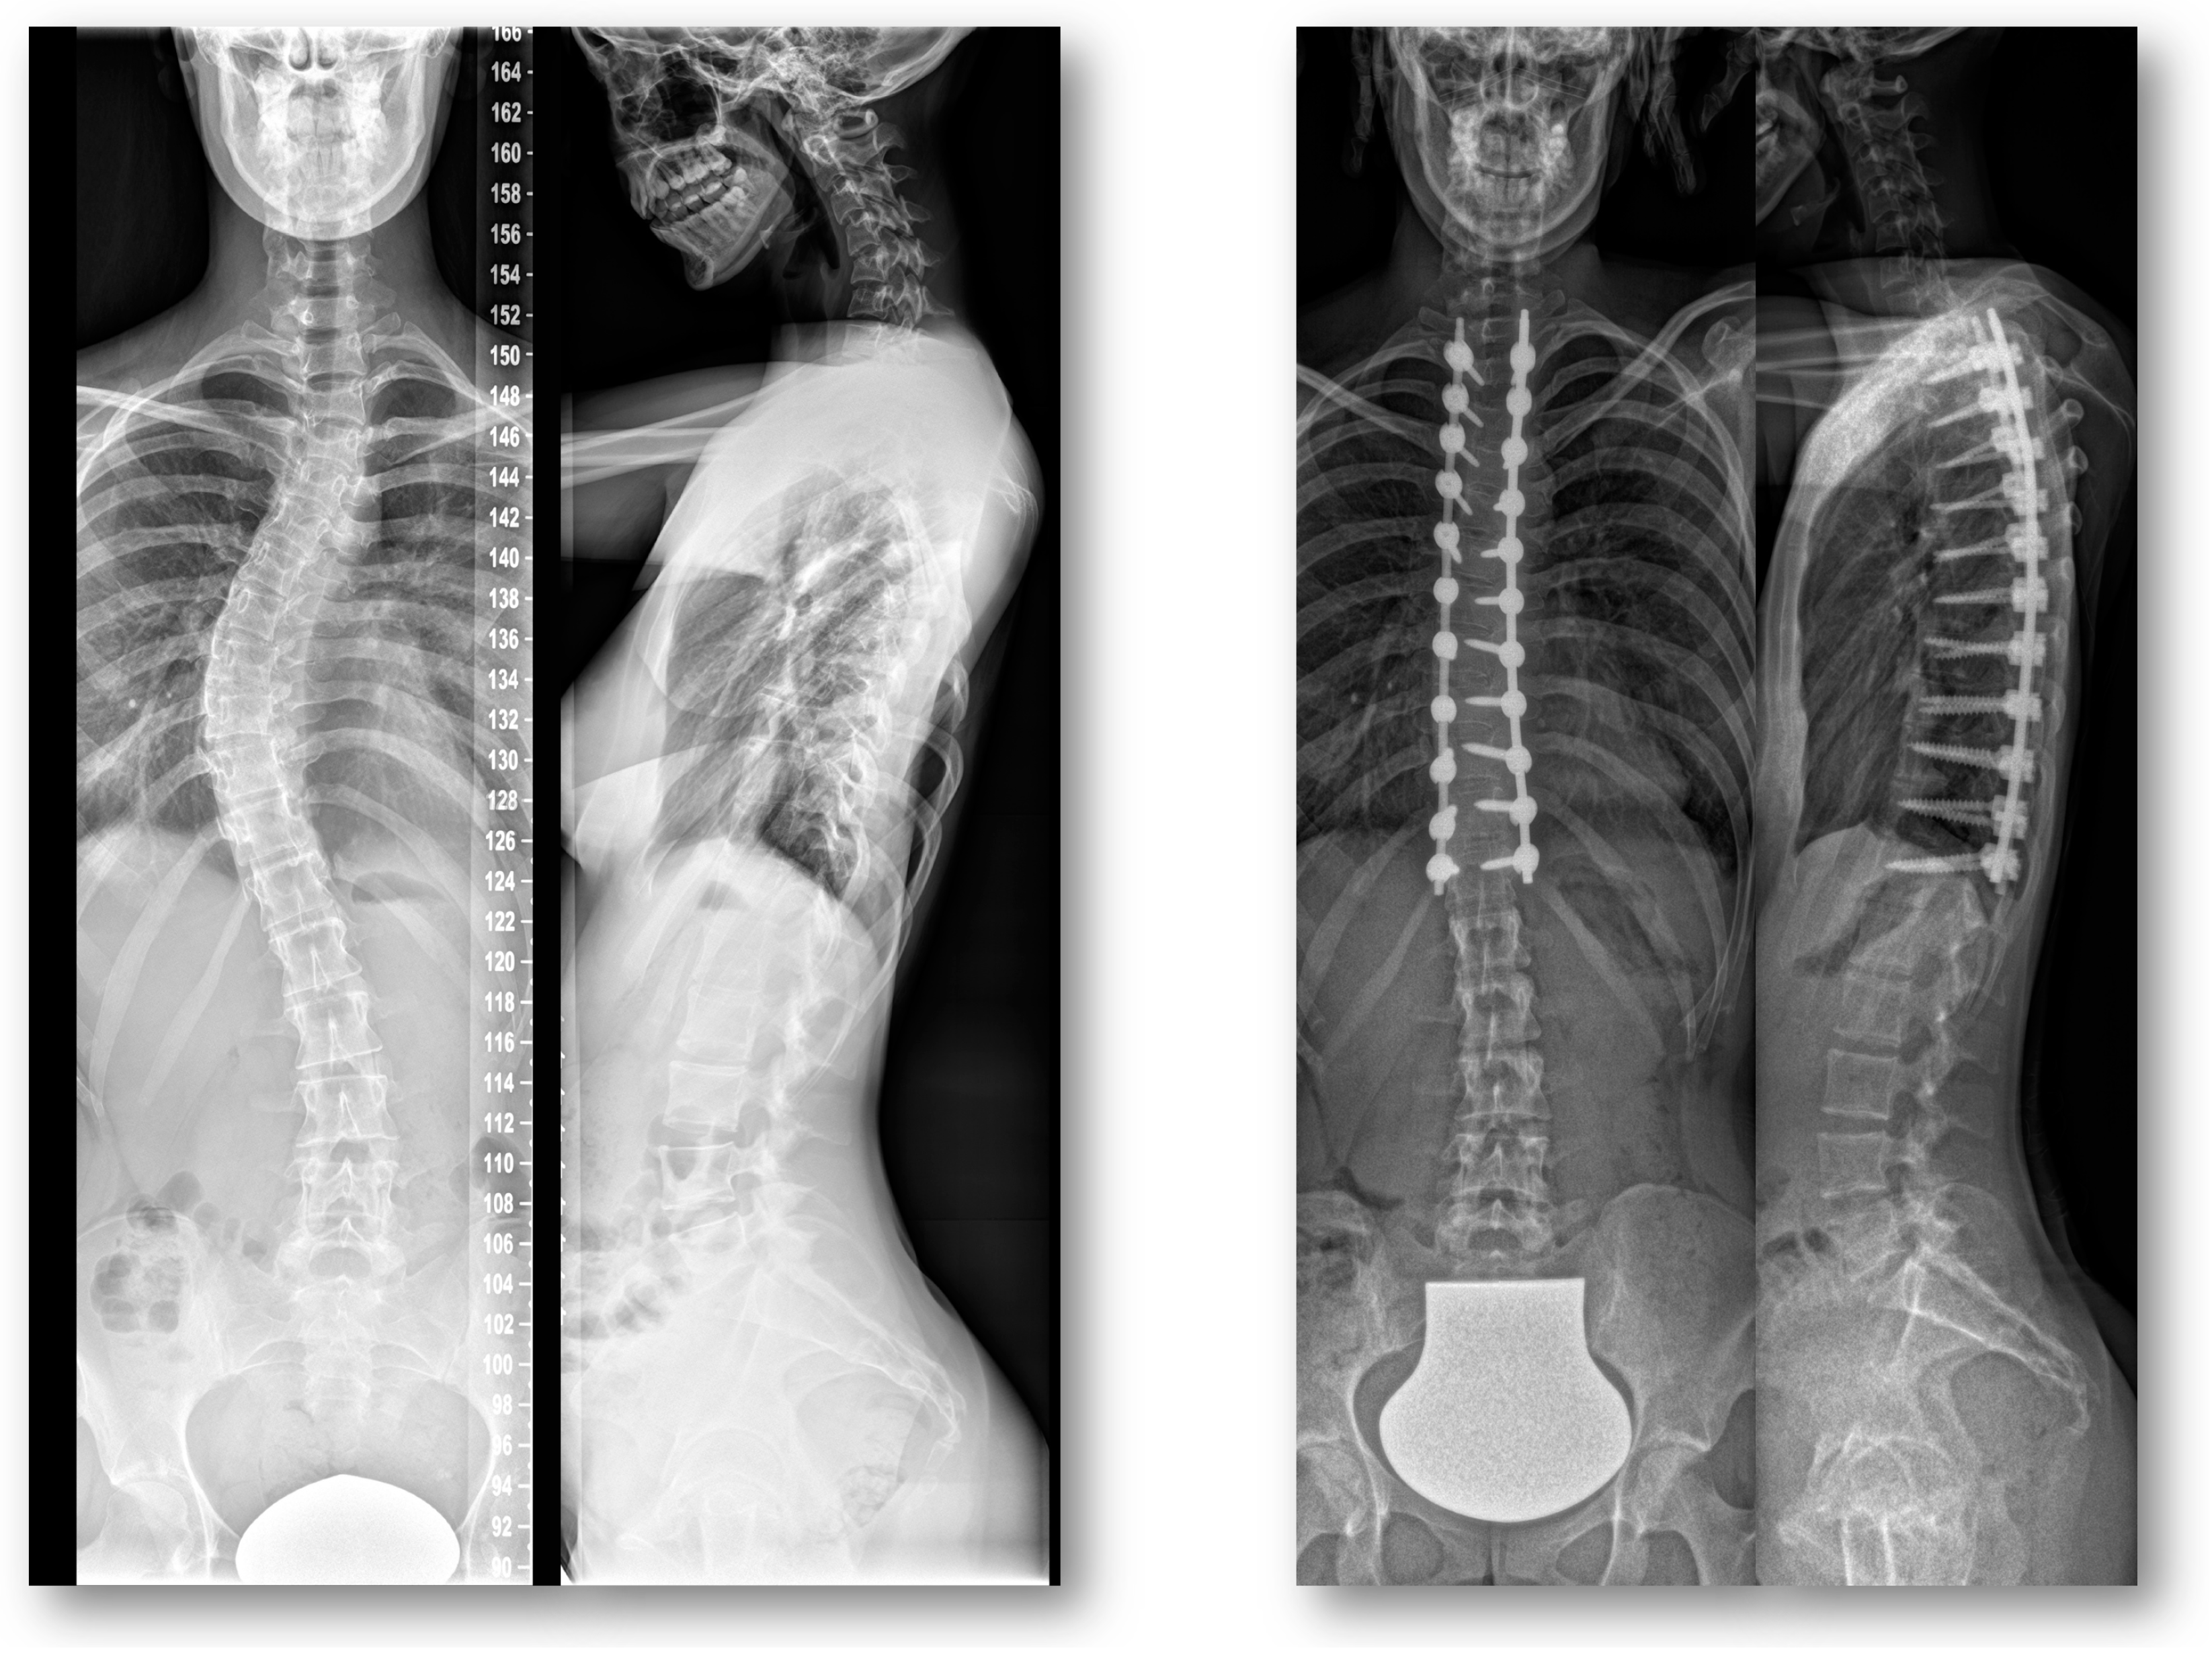

Return to Sport after Adolescent Idiopathic Scoliosis (AIS) Correction Surgery: A Retrospective Data Analysis

1. Introduction

2.3. Radiographic Assessment